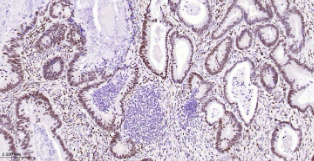

Immunohistochemical analysis of paraffin embedded Human colon cancer tissue slide using IHC0642H (Human p53BP1 Kit).